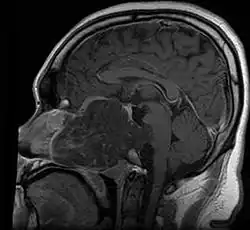

Anatomy

• In adults, remnants of notochord are present as the nucleus pulposus of the intravertebral discs, and distribution of tumors matches distribution of the remnants

• ~35% in sphenooccipital region (almost always involving clivus)

• Skull base:

• May be intracranial or extracranial, with mass effect symptoms depending on location

• Maximal resection followed by proton beam irradiation.

• Overall survival is dependent upon local control of disease. Prognostic factor for local control of disease is amount of residual tumor after original surgery (<25cc residual tumor is better).

• Clear margins are achieved in <50% of skull base chordomas.

• Doses of 70 CGE necessary for control of residual disease.